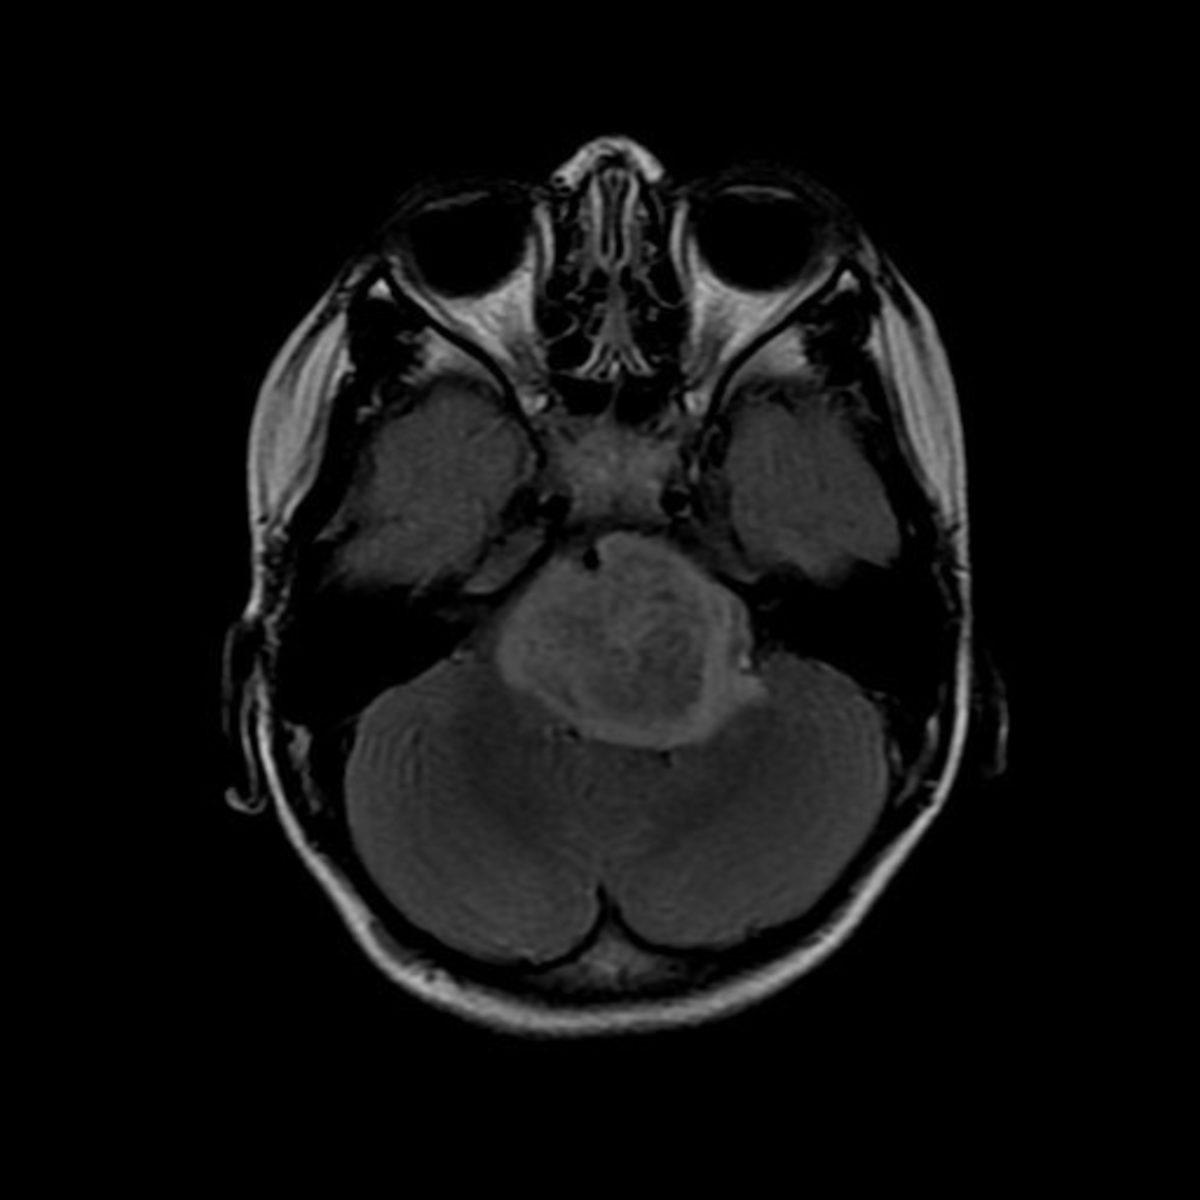

İçerikten Görseller